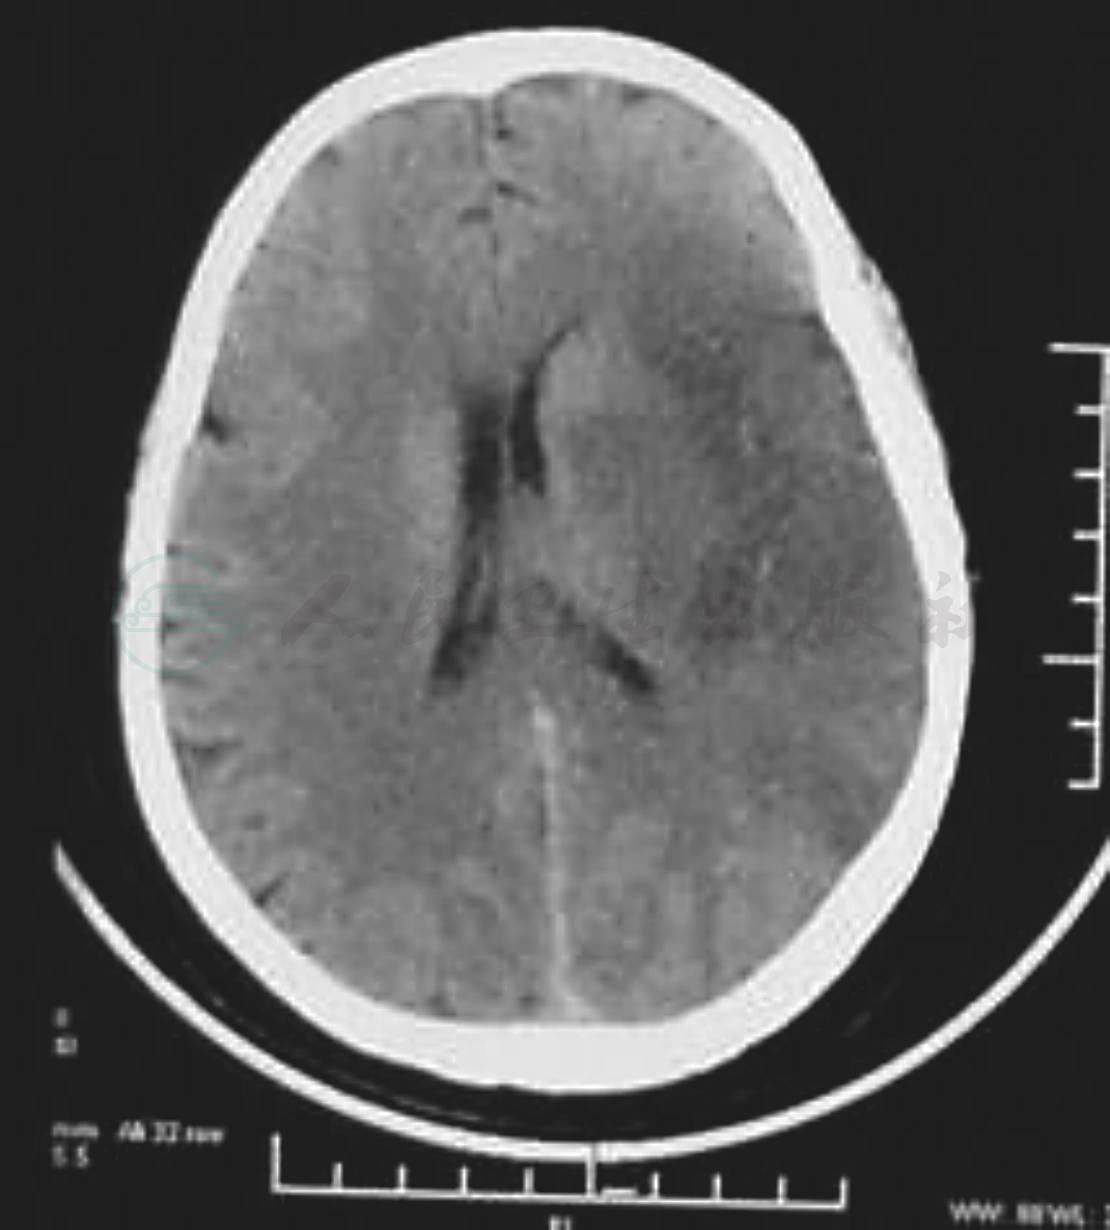

SIE症状逐渐发展,在几小时、几天、几周,甚至几个月内呈阶梯状或稳步恶化,常于6小时至数日内达高峰。DSA常显示颈内动脉或大脑中动脉闭塞(图1,图2分别为脑梗死发病12小时及72小时CT表现,左侧大脑中动脉区域低密度改变逐渐明显)。

图1 发病12小时CT

图2 发病72小时CT

缺血性脑卒中患者首先做CT扫描,可以区分脑缺血及脑出血。TIA患者CT扫描多无阳性发现,少数可表现为轻度脑萎缩或在基底节区有小的软化灶。RIND患者的CT表现可以正常,也可有小的低密度软化灶。CS患者则在CT上有明显的脑低密度梗死灶,可有脑室扩大。脑梗死初期CT一般不能发现缺血灶,24~48小时后低密度区才逐渐显现。MRI检查能够克服CT早期阴性结果的缺点,可以在脑卒中6小时后发现早期脑梗死部位。梗死灶呈长T1和长T2改变,表示存在细胞毒性脑水肿。在24小时左右,梗死灶内血-脑脊液屏障破坏,注射Gd-DTPA做MR增强扫描可见明显的信号增强。发病1周后梗死灶仍可表现长T1和长T2,但T1值较早期缩短。如梗死灶内有出血,呈T1值缩短而T2值仍然延长。